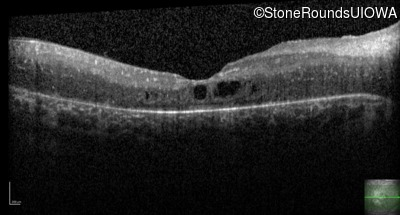

Age at visit: 17 years

This 17 year old female feels that the vision in her right eye has worsened since her cataract surgery 8 weeks ago.